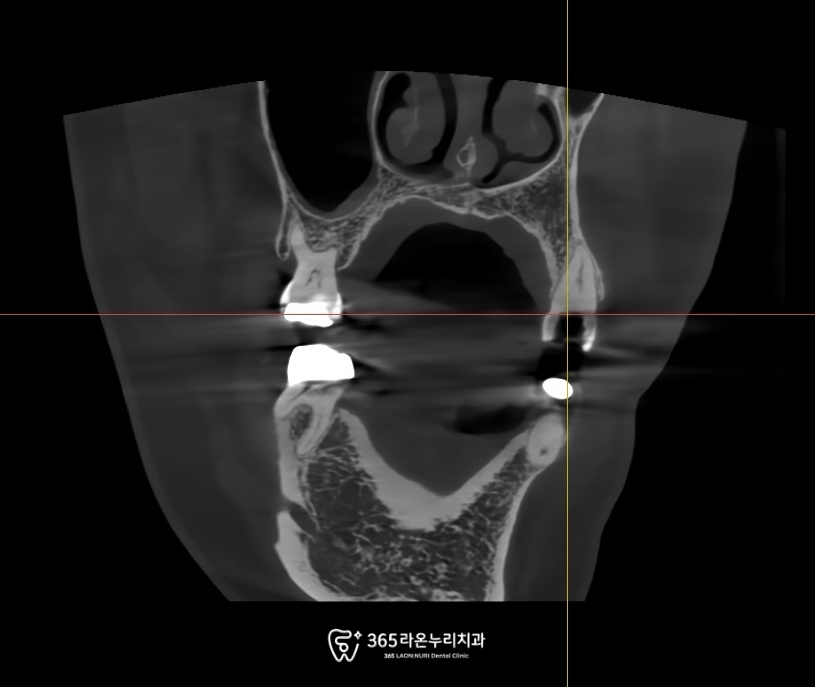

CT를 통해 더 이상

기능을 못하는 것을 확인하였습니다.

뿐만 아니라 비어있는 치아,

우식증이 심한 치아와

크랙이 있는 치아 등

문제점을 차근차근 해결하는

과정이 필요해 보입니다.